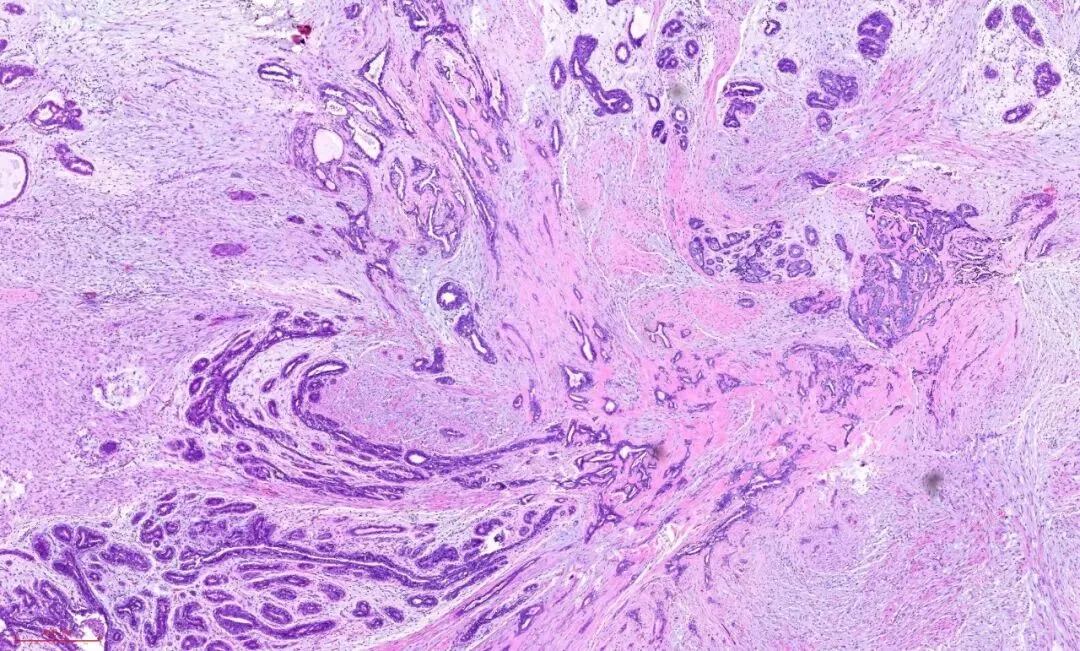

所以,即便是这样的杂乱无章,貌似癌的浸润,也还是良性的,这时应仔细观察细胞的异型性。如果是癌,细胞异型性是很大的,如下图:癌性的间质促纤维反应,也是粉染的,但不像硬化性腺病那样去挤压腺体,而是腺体与间质之间有一些裂隙,更大的区别在于细胞异型性,常有丰富的嗜酸性胞质,有不同的核级,核从规则到多形性,核大深染,核仁明显,核分裂象易见。如下图:

如下图:可查见导管内癌的成分。而硬化性腺病则没有。

所以,诊断时,尤其是在术中冰冻诊断中,硬化性腺病是时刻需要与浸润性癌鉴别的。低倍镜下看结构,高倍镜下看细胞,需要用心体会,总结如下: